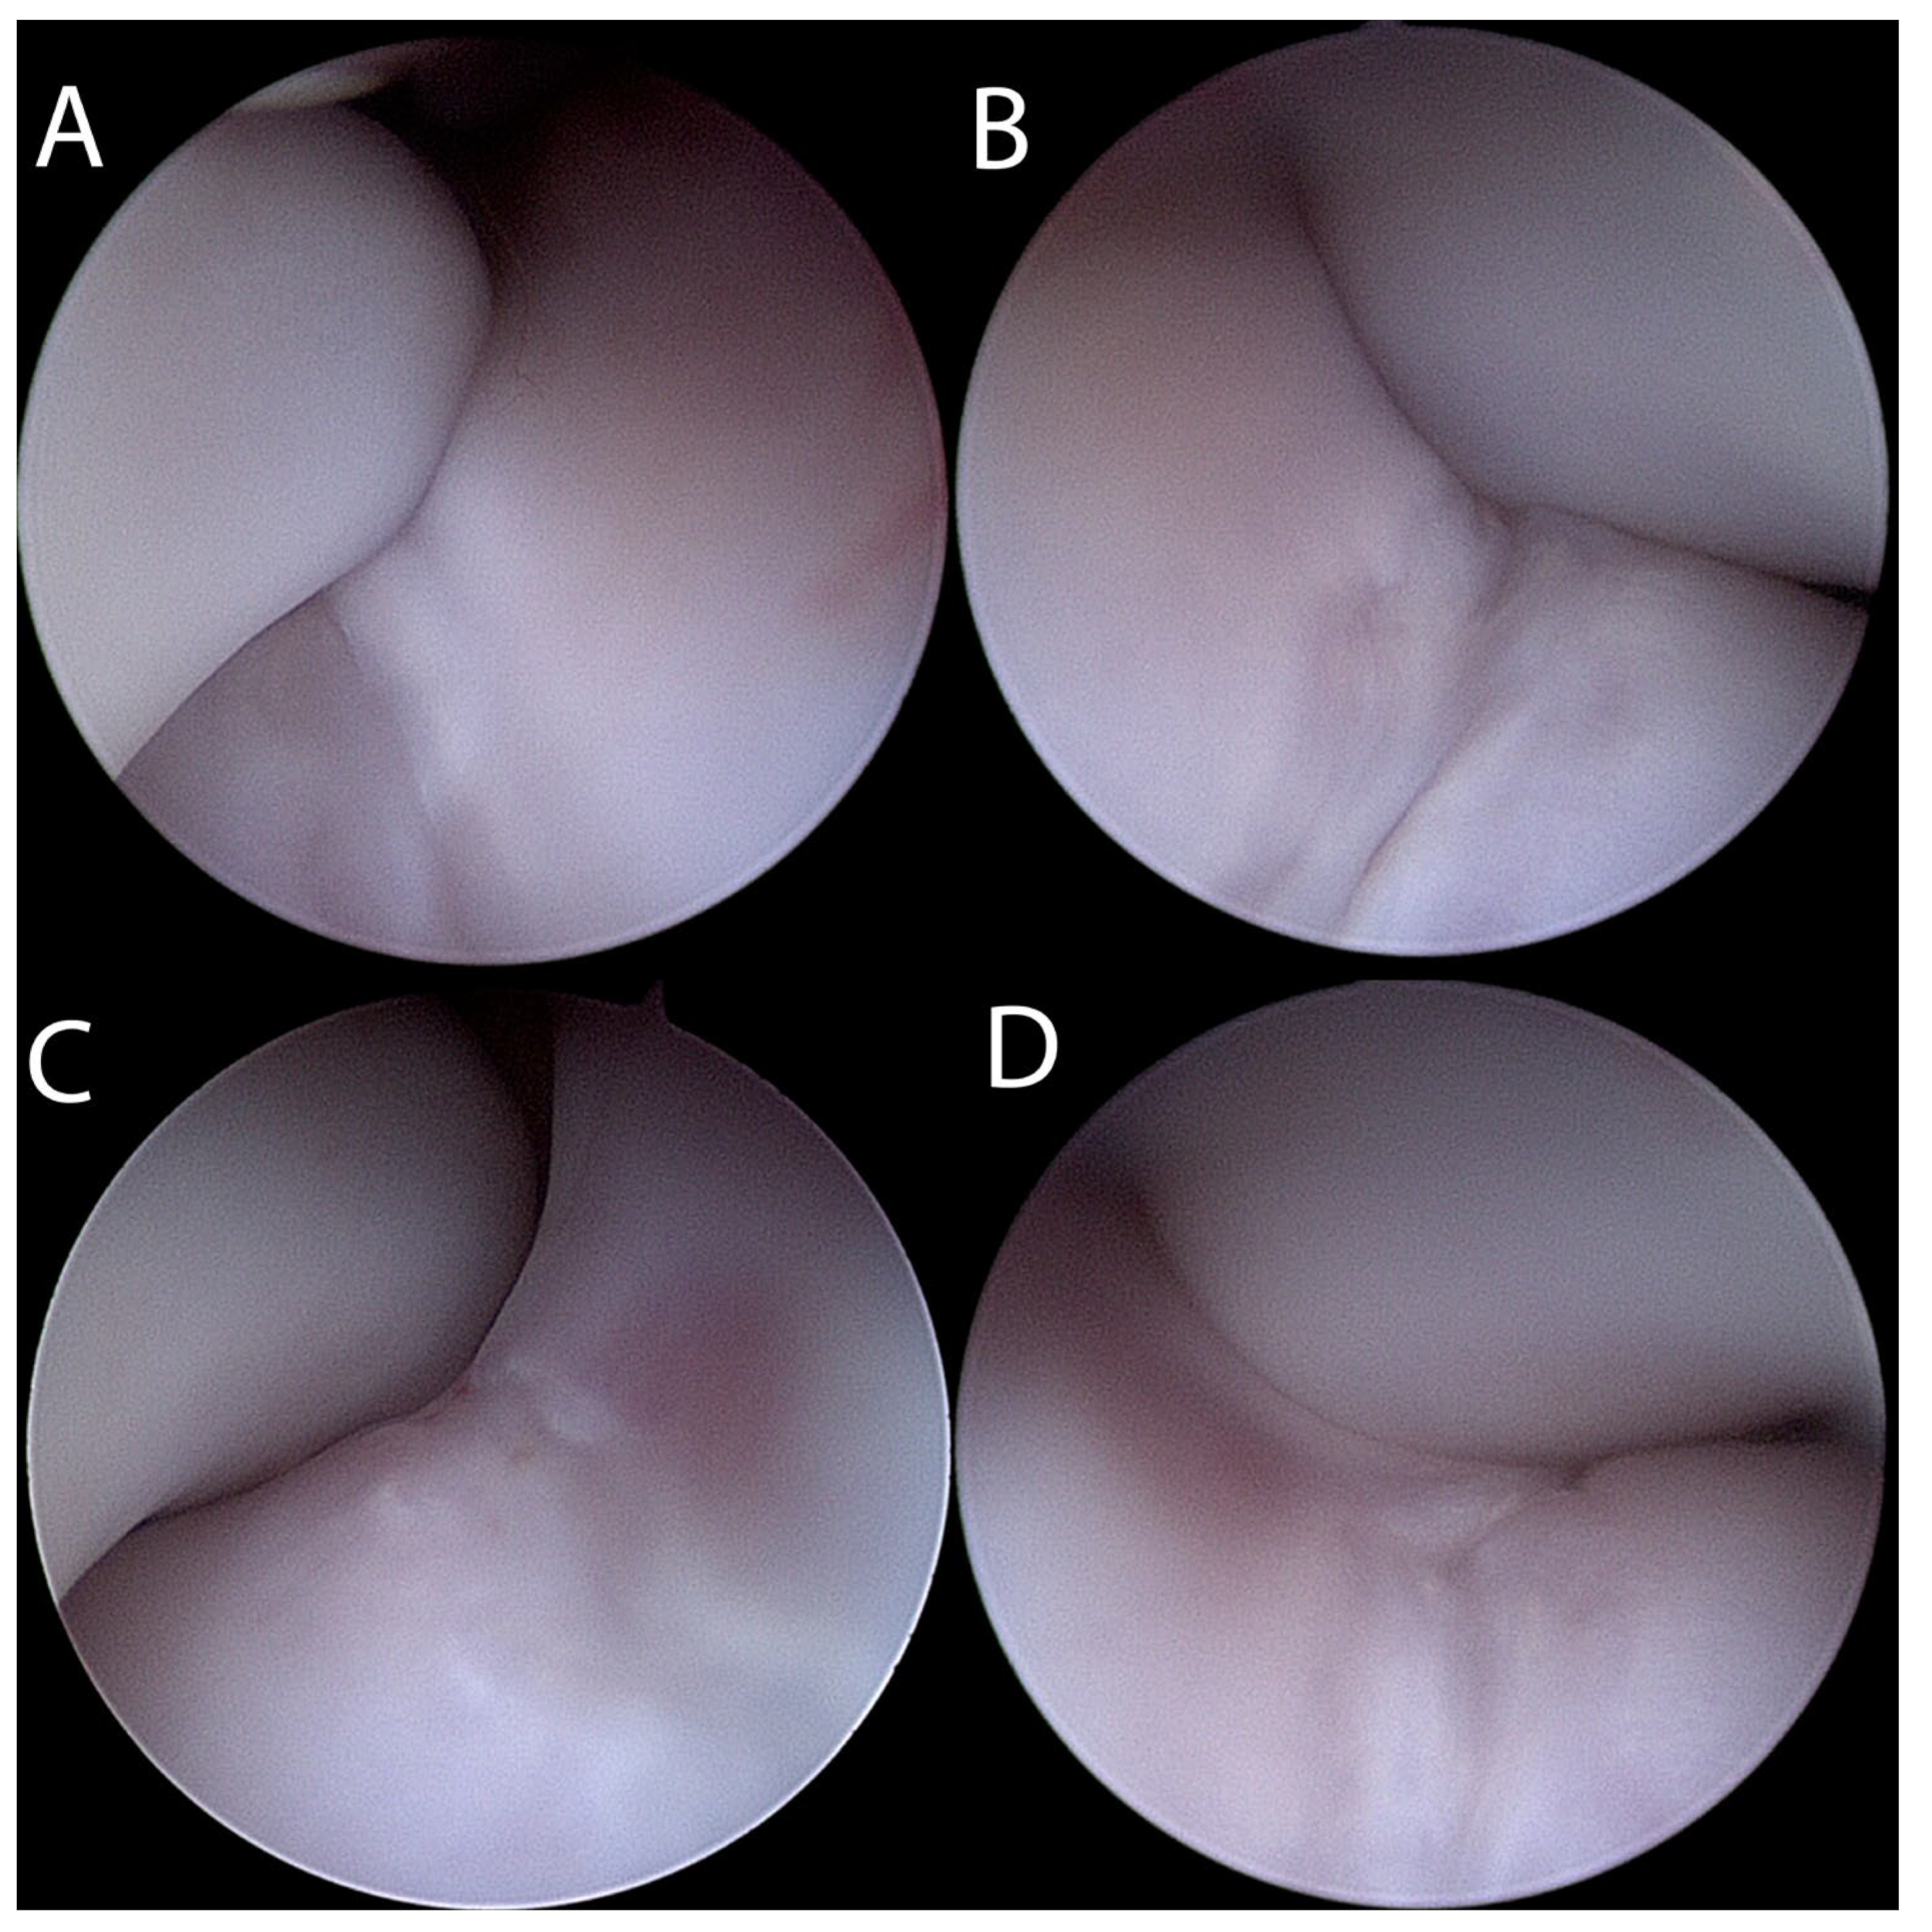

2. Materials and Methods

Surgical Treatment

3. Results